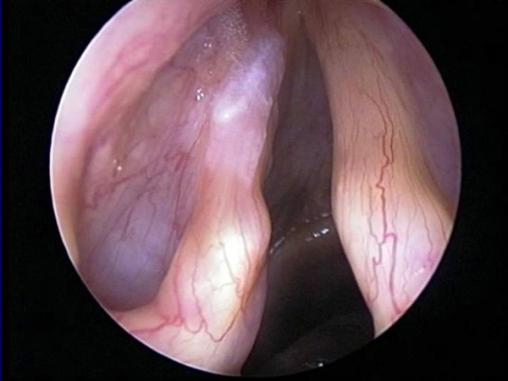

Leucoplasie de la corde vocale gauche

Il s’agit d’un état précancéreux.